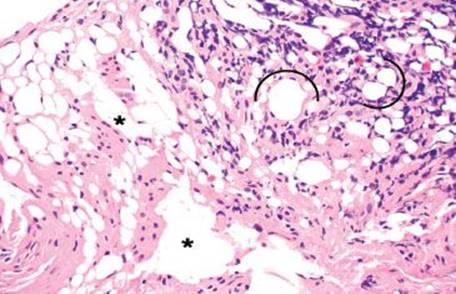

Figure 4.248 Air artifact. An alternative field shows large, bizarre air pockets (asterisks), which dissect the resident tissue. Lipomas do not tend to percolate around native structures such as ganglion cell clusters, nerves, fibrous tissue, and blood vessels, as seen in this example of an air artifact. Also, there is no epithelial lining and no nuclei to suggest a lymphovascular space or adipocytic lesion, respectively.

Figure 4.263 Muciphages. Muciphages are benign oddities, most commonly seen in the rectum. They can be spotted at low power, as in this case.